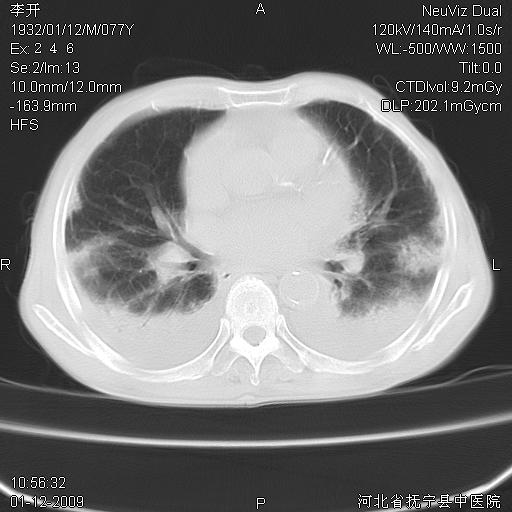

以下是引用黑白光影在2009-1-19 16:49:00的发言:[br]心衰肺水肿;心包、胸腔积液;冠脉钙化;肺部感染。